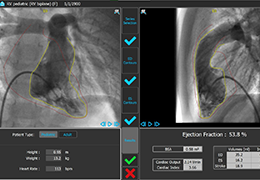

View X-Ray CT & MRI Scans Fast and Easily

Designed for surgeons, Pro Surgical 3D makes it easy to view patient scans quickly. Pro Surgical 3D facilitates the optimal 3D treatment and assessment workflows based on X-ray CT and MRI scans – and best of all, it’s FREE!

Everyone – including surgeons, patients and their loved ones – benefits from being better informed by the wealth of information buried within CT and MRI scans. Pro Surgical 3D gives surgeons more information to develop optimal treatment plans for patients. It also helps patients and their support group better understand their medical condition and proposed treatment options.

Traditional multi-planar slicing

High-quality and fast 3D reconstruction and 3D rendering